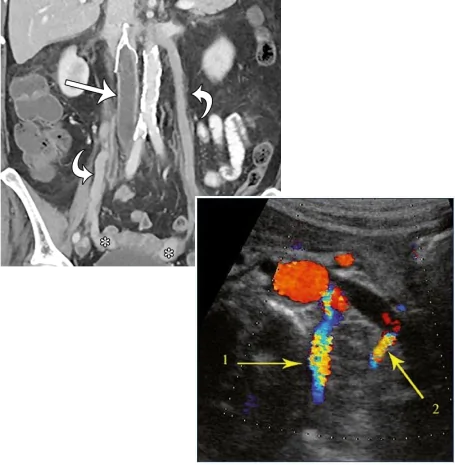

The vascular specialists at Pedes Orange County use a combination of advanced imaging techniques to accurately diagnose pelvic venous disease including pelvic venous congestion syndrome in our patients. These imaging techniques include:

- Pelvic or abdominal ultrasound

- Pelvic or abdominal CT and MRI scans

- Pelvic venography using X-ray imaging

At Pedes Orange County, our vascular doctors use a combination of advanced imaging techniques to accurately diagnose pelvic venous disease including May-Thurner Syndrome in our patients. These

imaging techniques include:

Pelvic venography using X-ray imaging

Abdominal and pelvic ultrasounds help visualize backflow in ovarian veins. But it doesn’t provide enough information, and therefore, CTs and MRIs may be used to take further images. CTS and MRIs help evaluate the pelvis

In some situations, ultrasound alone may not provide all the necessary information, and your physician may want to obtain additional imaging. For example, CT and MRI are used to take detailed pictures.